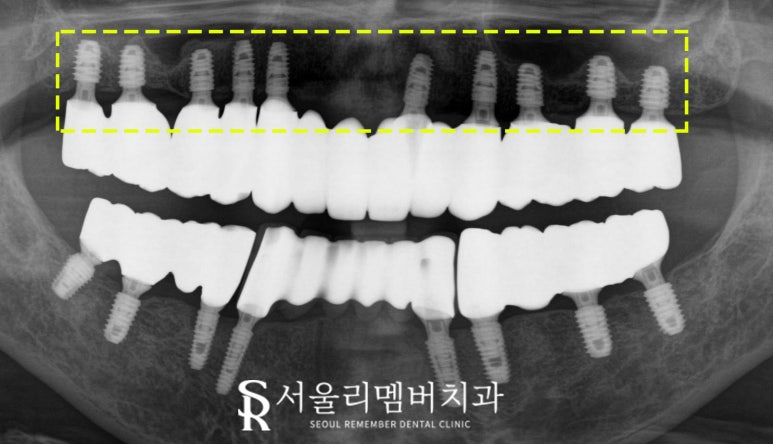

- 완성

파노라마 엑스레이 사진을 보면

픽스처의 방향, 위치와 깊이, 서로 간에

간격이 깔끔하게 식립 된 것을 볼 수 있습니다.

크라운도 자연치와 같이 색조도 조화롭습니다,

정상교합으로 서로 맞물린 모습을

볼 수 있습니다.

특히 위아래 전악 교합도

신경 써서 맞춰야합니다.

교합이란 치아의 맞물림을 말합니다.

물리는 힘이 골고루 배분되어 균형을 이루고 있으면,

저작능력이 좋아지고

implant도 오랫동안 건강하게 쓸 수 있습니다.

만약 교합이 흐트러지거나

통증으로 한쪽으로만 사용해서

교합이 틀어지면

보철에 문제가 생길 수 있고, 더 나아가면

턱관절에도 영향을 줄 수 있기 때문에

섬세하고 세밀하게 여러 번 조정해야 합니다.